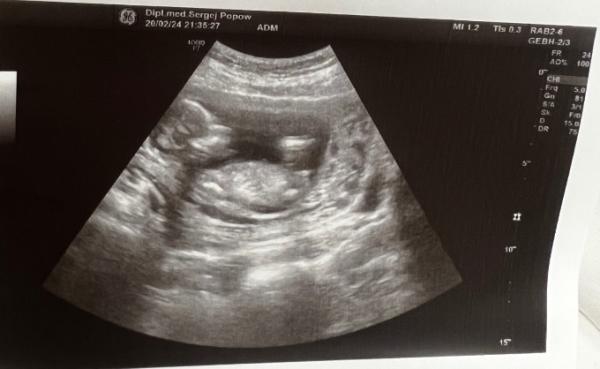

Hi ihr Lieben :) bin aktuell in der 15. SSW (14+5). Das Bild ist von heute von einem Vertretungsarzt mit schlechterem Gerät. Habe bei der Nackenfaltenmessung letzte Woche eine Tendenz zum Geschlecht bekommen und wollte euch mal nach eurer Meinung fragen ich versuche auch noch ein Bild von letzter Woche in die Antwprten zu packen.

Foto von heute von unten geschallt

Foto von der Nackenfaltenmessung bei 13+6

Also laut dem nub auf dem ersten Bild würd ich sagen: Mädchen Was sagt denn der Arzt :)?